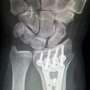

Some lovers try positions that they can't handle—I'm referring to the bones of the wrist, of course. The phrase is a classic mnemonic used to remember the eight carpal (wrist) bones—scaphoid, lunate, triquetrum, pisiform, trapezium, trapezoid, capitate and hamate—whose initials form the memorable sentence.